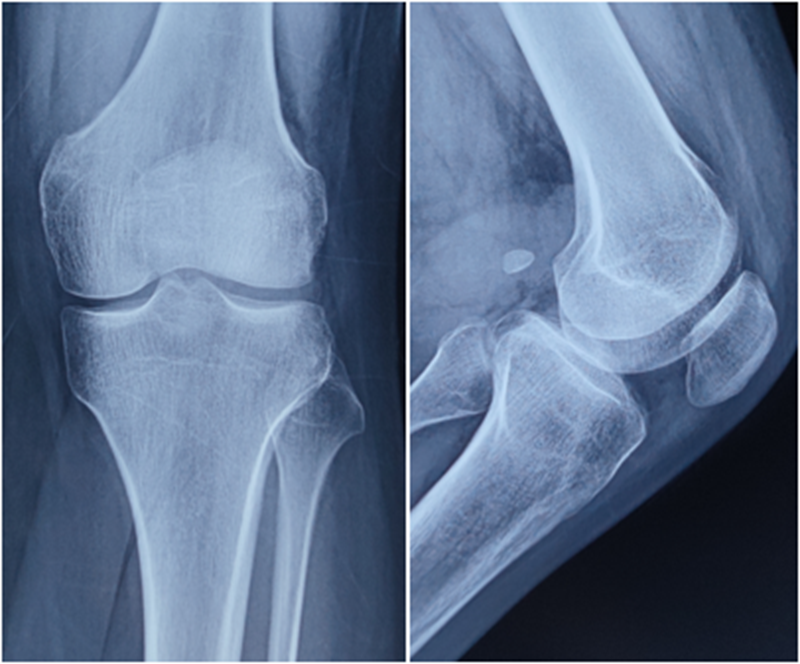

典型病例,张X,男,18岁,因扭伤致左膝关节疼痛伴活动受限1月余入院。

诊断:1.左膝前交叉韧带损伤;2.左膝外侧半月板损伤合并囊肿。

术前X线

术后X线